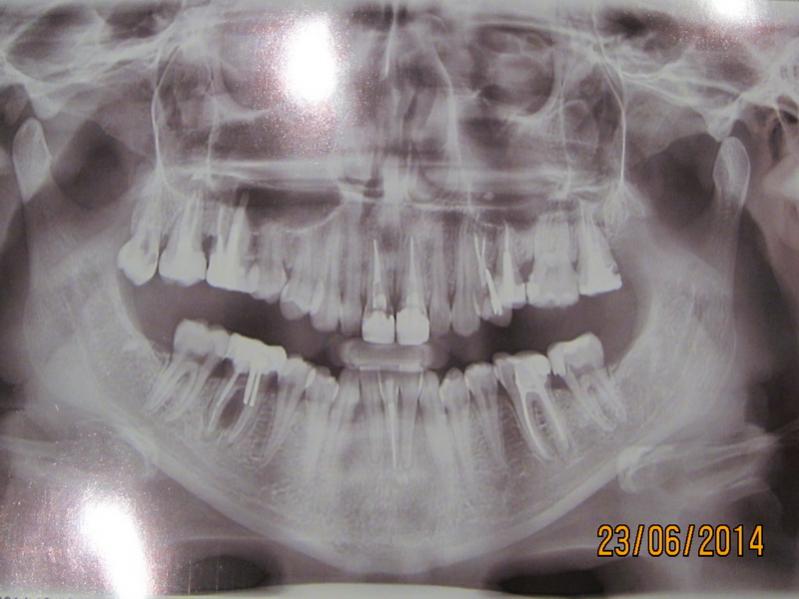

Нажмите на изображение для увеличения

Название: 22.jpg

Просмотров: 26

Размер:	48.5 Кб

ID:	8331116Нажмите на изображение для увеличения

Название: 11.jpg

Просмотров: 30

ID:	8331119Господа Стоматологи,пож-ста,посмотрите снимки и прокомментируйте.

а что тут комментировать? с вероятностью процентов в 95 нижней 6-ке можно сказать до свидания.. 5% оставляю для маньяков, которые долго и мучительно захотят воевать с перфорацией медиального корня и ее последствиями.. соседний с ней 5 - полость на контактной поверхности

7-й снизу с противоположной стороны - необходима замена пломбы, верхние с той же стороны - корекция пломб в 7 с дистальной стороны, замена пломбы в 6 и 5 с адекватным восстановлением контактного пункта между ними, 4-й - хочется прицельный снимок посмотреть. Верхние с противоположной стороны - в 8 есть полость на контактной поверхности (но надо еще во рту смотреть внимательно), 6-й хотелось бы прицельный снимок.

18,46 удалять.

Ортодонтия.

Имплантация 46.

Коронки 17,16, 11, 21, 24, 25, 27, 36.

Коронка на имплантат 46.

Ирригатор в подарок.

Шинирование после ортодонтии.